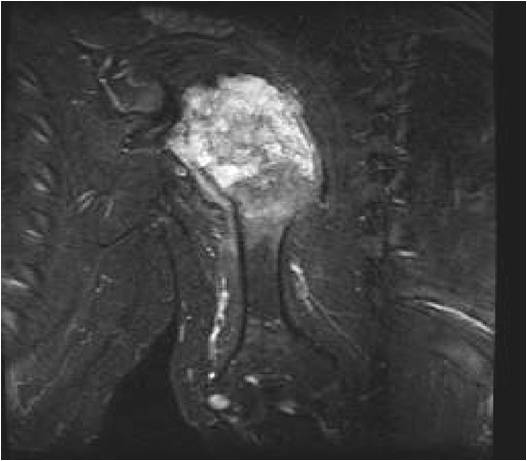

- MRI

- Lobulated margin

- Marked increased intensity long TR images

- Calcified chondroid – low intensity all sequences

MRI:

- Lobulated margin (Lobular Growth Pattern)

- T1 Weighted Images: Intermediate Signal Intensity

- Calcifications will be low signal

- T2 Weighted Images: High Signal Intensity

- High water content shows as high signal on T2 weighted images

- There should never be any cortical destruction nor a soft tissue component. If this exists then the tumor must be a chondrosarcoma.

- Endosteal scalloping and cortical expansion is acceptable for phalangeal tumors. In most benign long bone cartilage tumors there is minimal endosteal scalloping but there should be no cortical expansion nor thickening. There should be no cortical destruction and no soft tissue component associated with an enchondroma. Cortical destruction, periosteal thickening, cortical expansion and a soft tissue component indicates a chondrosarcoma of the long bone.